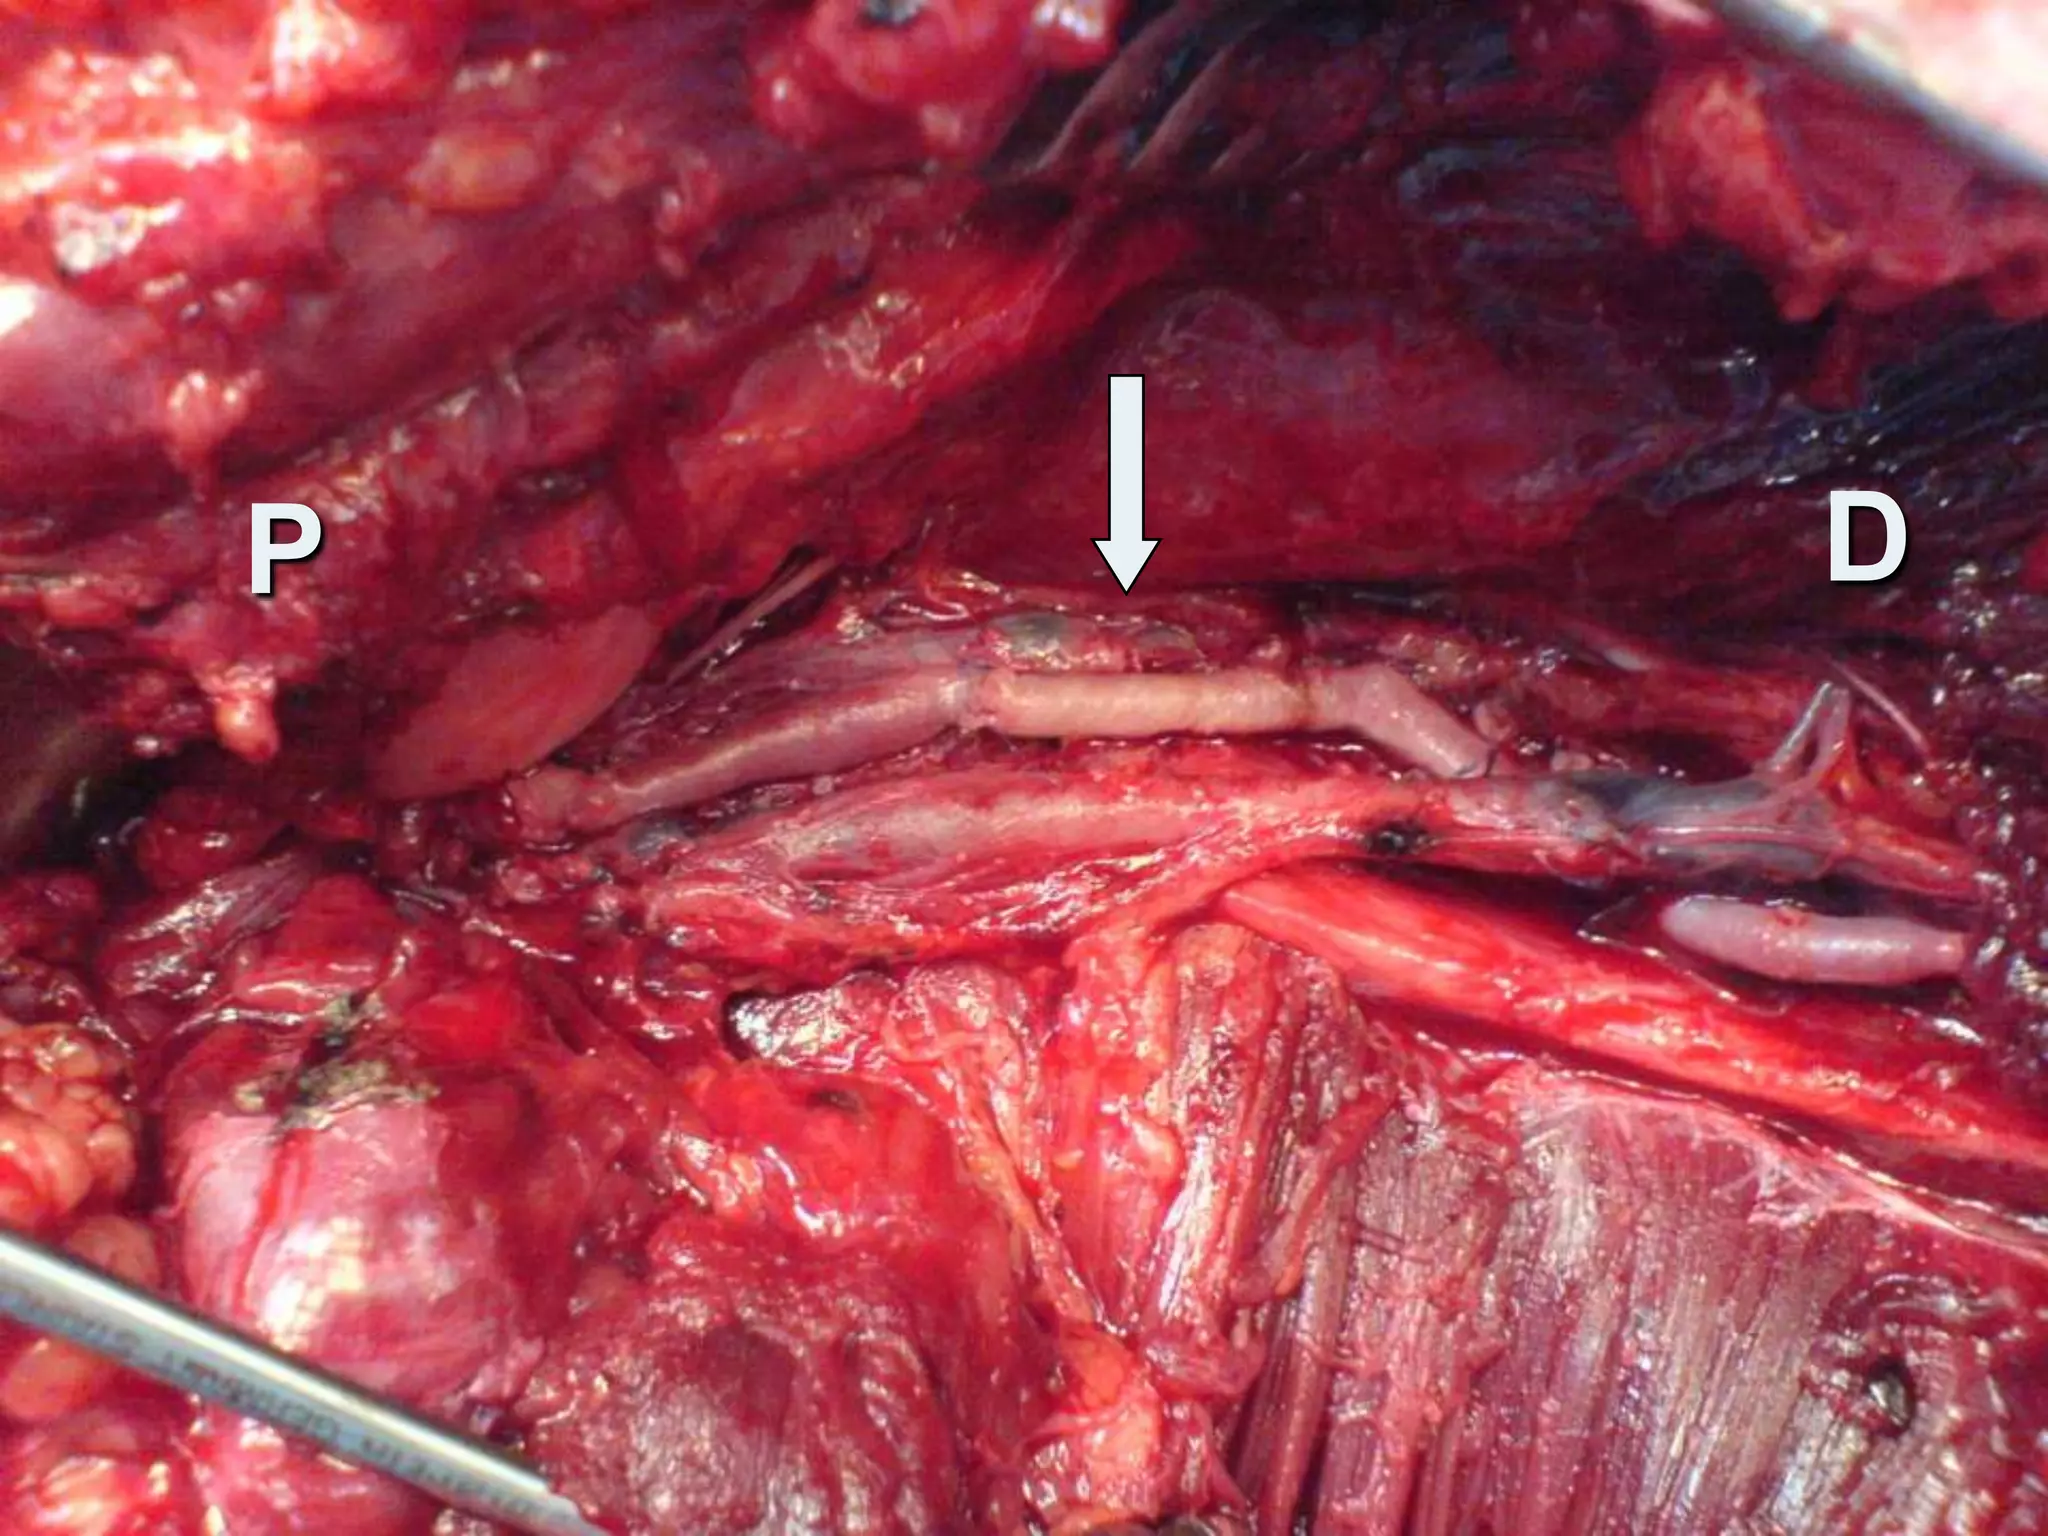

Intra-operativelyTotally transected A.Tibial atrey     (crushed distally)Contusion thrombosis T.P trunkLigation of A.Tibial artery Excision of the contused T.P trunkEmbolectomy with Fogarty cathInterposition vein grafting

Intra-operativelyTotally transected A.Tibialatrey (crushed distally)Contusion thrombosis T.P trunkLigation of A.Tibial artery Excision of the contused T.P trunkEmbolectomy with Fogarty cathInterposition vein grafting